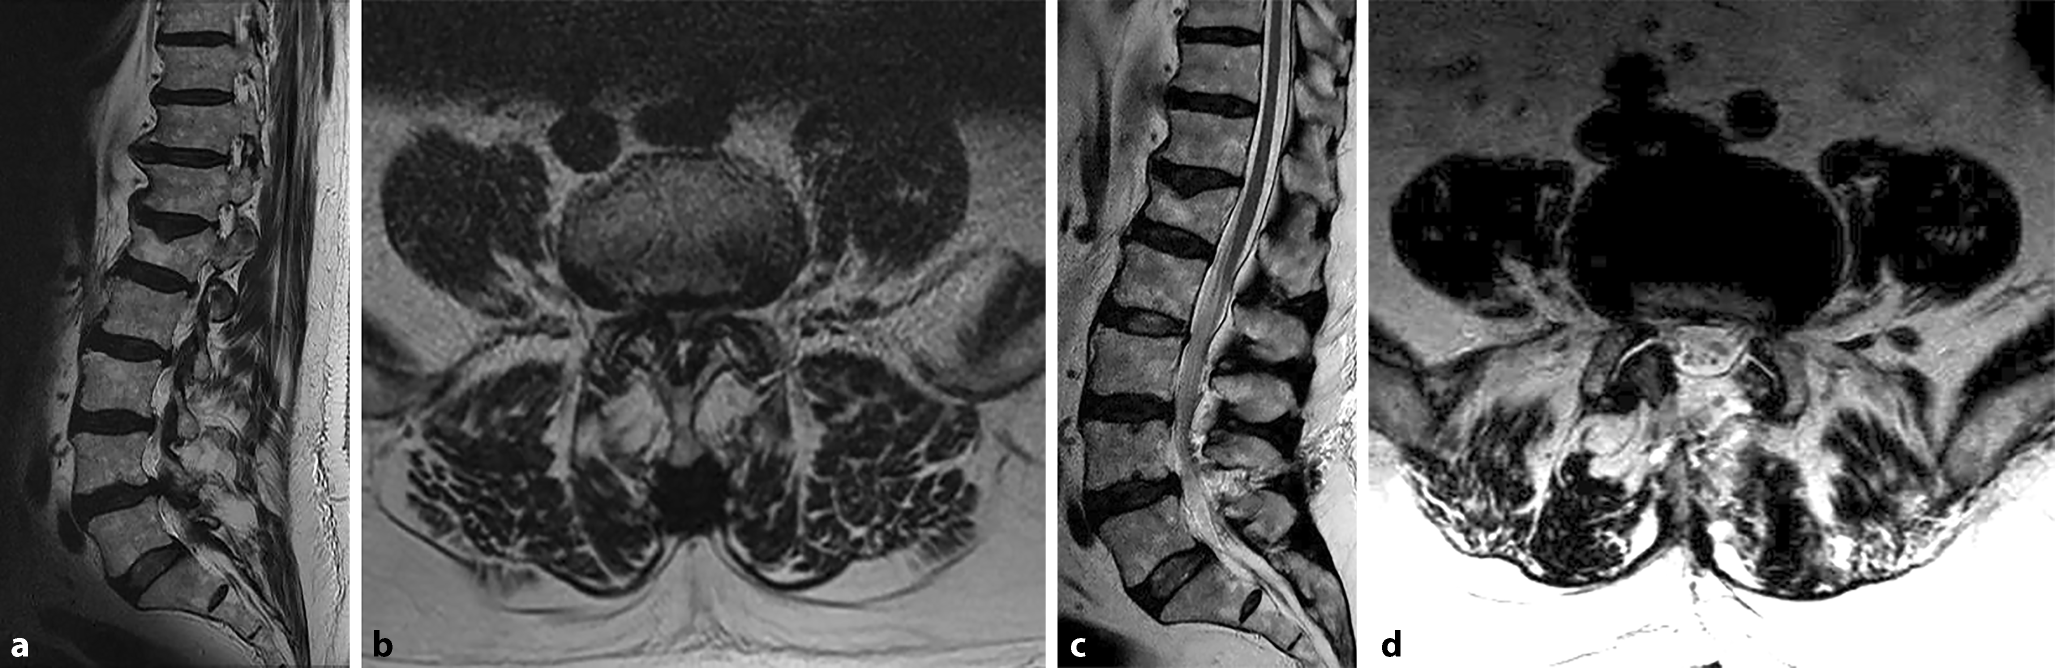

Figure 5 Lumbale Spinalkanalstenose Springerlink